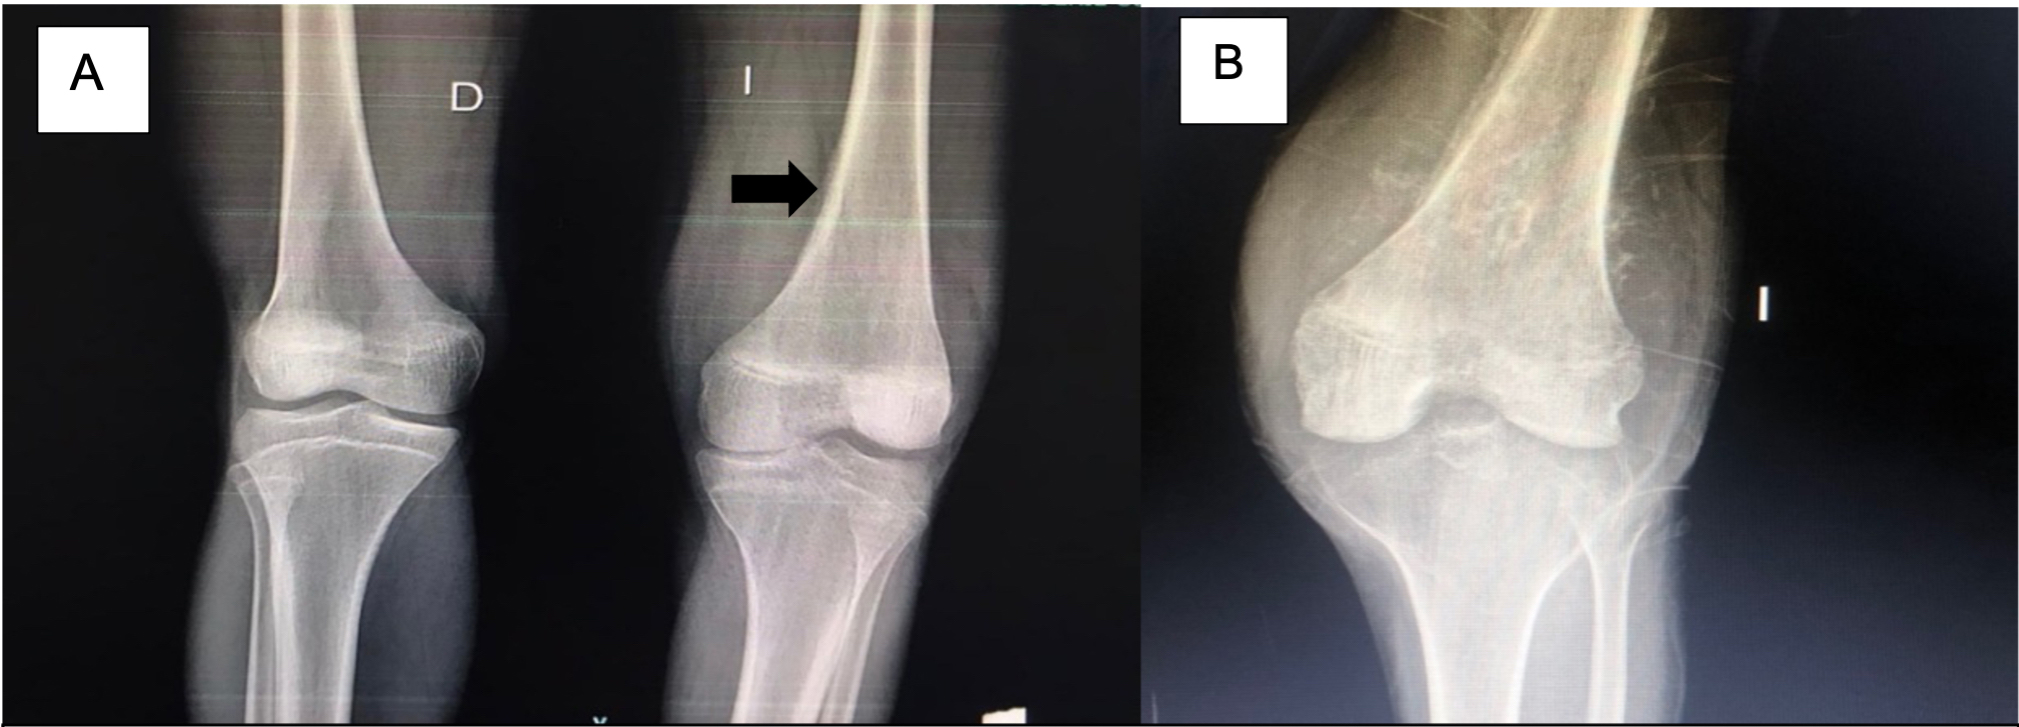

En la radiografía de miembro inferior izquierdo (MII) se aprecia disminución del espacio femorotibial interno con reacción perióstica cortical anterior en tercio distal del fémur y triangulo de Codman (Ver figura 1). En la resonancia magnética nuclear (RMN) de MII con contraste, se observa una lesión de aspecto tumoral a nivel distal del fémur y compromiso del núcleo de crecimiento medial e hidroartrosis (Ver Figura 2). En la gammagrafía ósea se aprecian lesiones blásticas hipercaptantes en diáfisis proximal de humero derecho, espina iliaca anteroinferior, fémur en su diáfisis distal, rotula y tibia izquierda (Ver figura 3). La tomografía axial computarizada (TAC) de tórax y abdomen contrastado fue reportada como normal. El ecocardiograma doppler también fue reportado como normal.

Figura 1. Radiografía de rodillas comparativas.

A. Reacción perióstica cortical anterior en tercio distal de fémur izquierdo y triangulo de Codman. B. Masa pétrea de gran tamaño en tercio distal izquierdo.